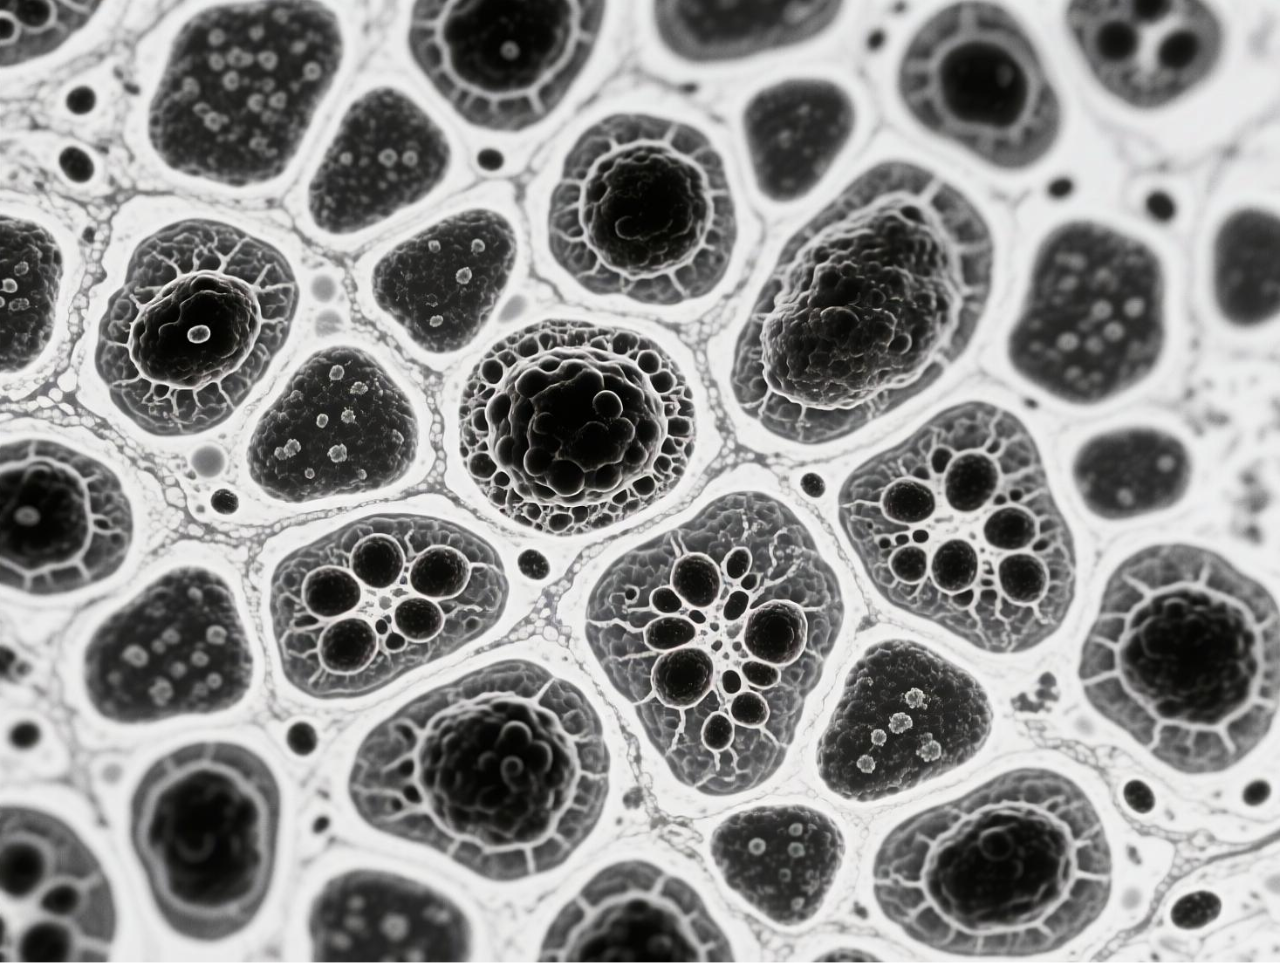

圖 BCG-MBs的制備與表征

臺式掃描電鏡在本研究中發揮了關鍵的表征作用,為微氣泡系統的結構驗證提供了直觀而精確的證據。研究團隊使用澤攸科技ZEM18臺式掃描電鏡對凍干后的BCG-MBs進行金濺射鍍膜處理后,在不同放大倍數下觀察其表面形態,清晰地展示了微氣泡規則的球形結構以及BCG在微氣泡表面的不規則分布狀態。這一表征不僅確認了微氣泡制備工藝的成功,還直觀揭示了BCG在微氣泡中的物理分布特征,為理解藥物釋放機制提供了結構基礎。掃描電鏡圖像作為重要的形態學證據,有力支持了后續對微氣泡浮力特性、藥物釋放行為及生物效應的分析,是連接材料設計與功能驗證的關鍵環節。